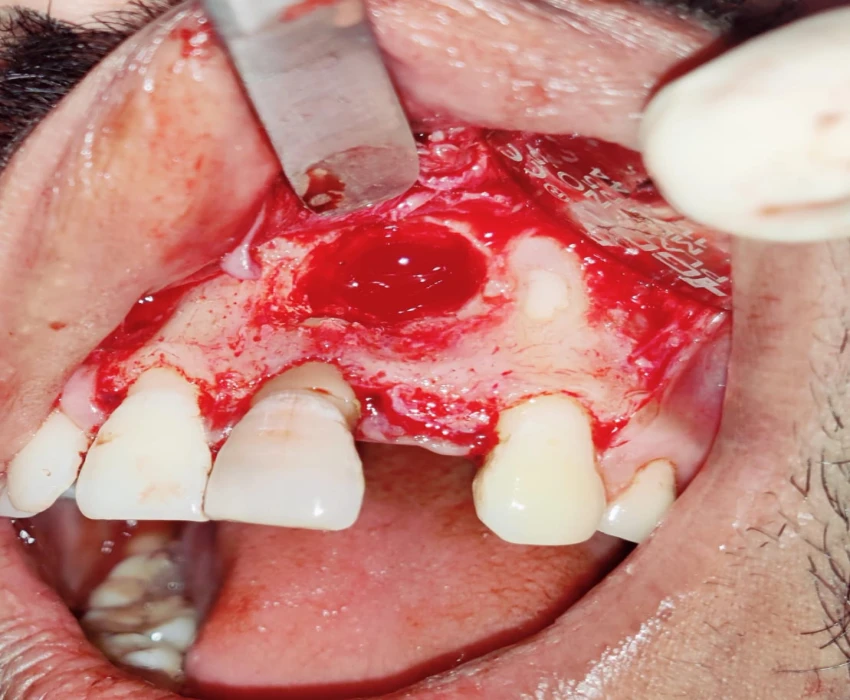

TREATMENT- Faulty prosthesis is removed in respect to 22, with the help of tapered fissure. Access Opening is done' in respect to 21, under La. Working length is determined . Canals are prepared using Hyflex CM and obturated using Gutta percha using lateral condensation. Microperiosteal flap is raised. Window preparation irt 21 , periapical curretage apicoectomy is done irt 21 followed by retrograde filling with bioceramic. Cavity is filled with bone graft. Sutures placed.